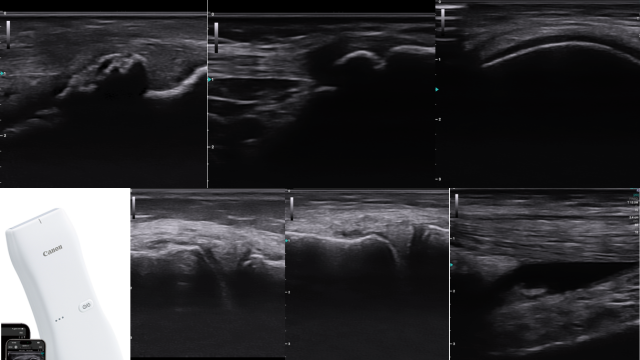

当院での膝治療

膝の痛みは、スポーツや日常生活での怪我、加齢による変形など、さまざまな原因によって起こる場合があります。

症状はもちろんのこと姿勢や動作を確認。エコーを使用し炎症などの状態も観察します。体の柔軟性や筋力の偏り、身体のバランスなどが原因となって障害が発生することがあります。体トータルでの確認が大切です。